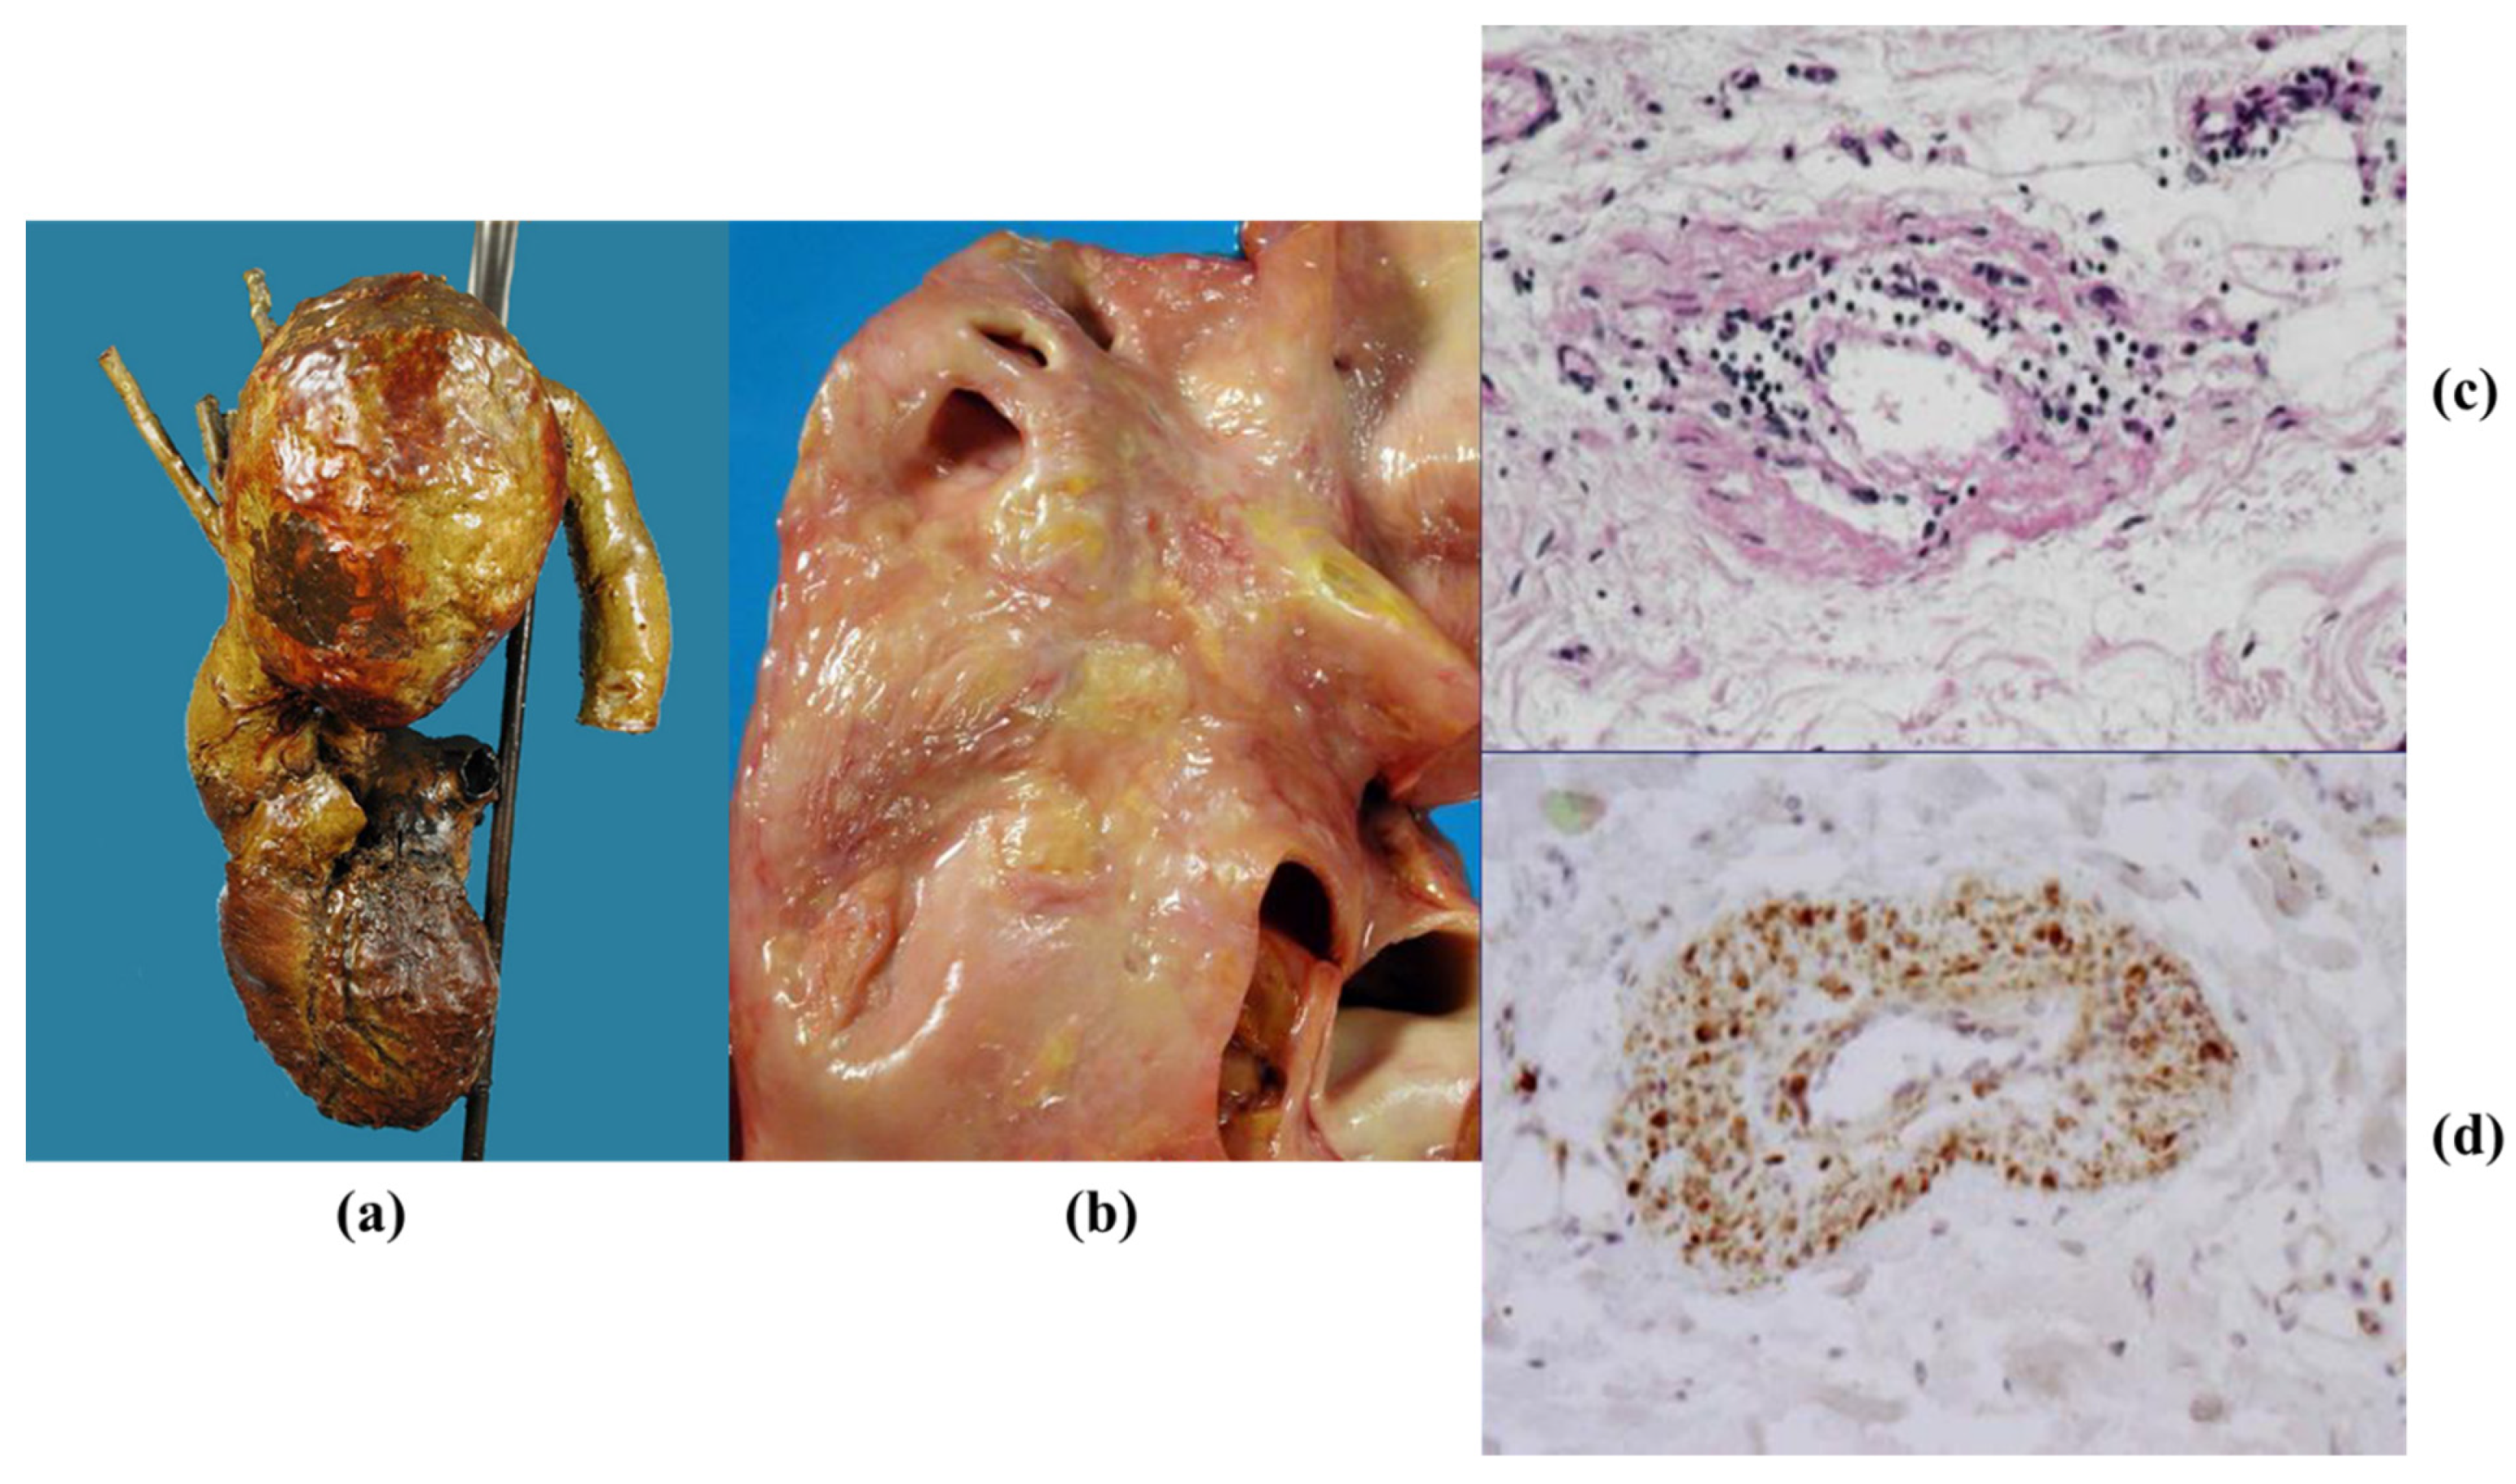

3.4. Inflammatory Diseases of the Aorta

3.5. Neoplasms